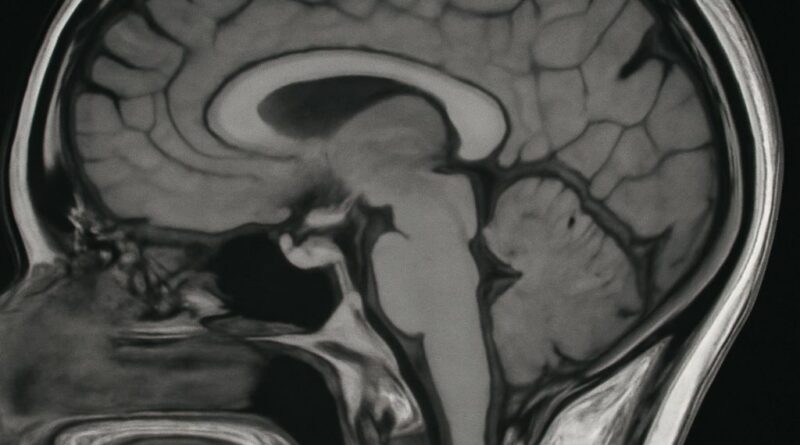

Read MoreHow to Read an MRI: A Patient-Friendly Guide to MRI Images Waiting for MRI results can be stressful, and many